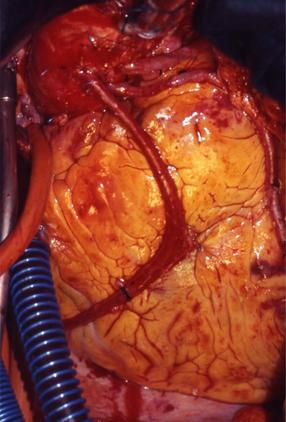

IMPIANTO ARTERIA MAMMARIA INTERNA